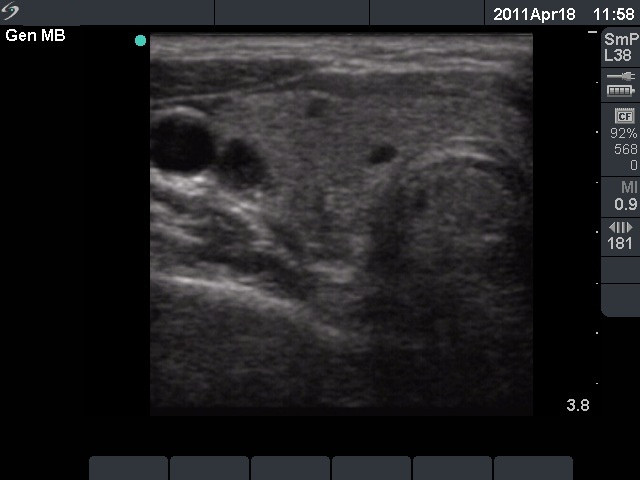

Initial examination (first row of images):

Clinical presentation: A 29-year-old woman requested a second opinion. She was in the 11th week of her pregnancy. She had mild neck discomfort for 2 months. A suspicious nodule was found in the left lobe on the evaluation. Aspiration cytology was repeatedly non-diagnostic. She was told that she had thyroid carcinoma with great probability. Her endocrinologist recommended to abort the child and then to undergo thyroidectomy.

Palpation: The left thyroid was hard on palpation, but not painful.

Ultrasonography: The right thyroid was echonormal and contained several small, insignificant lesions. There was a hypoechogenic lesion with blurred borders in the central and in the ventro-medial part of the left thyroid with increased intranodular blood flow.